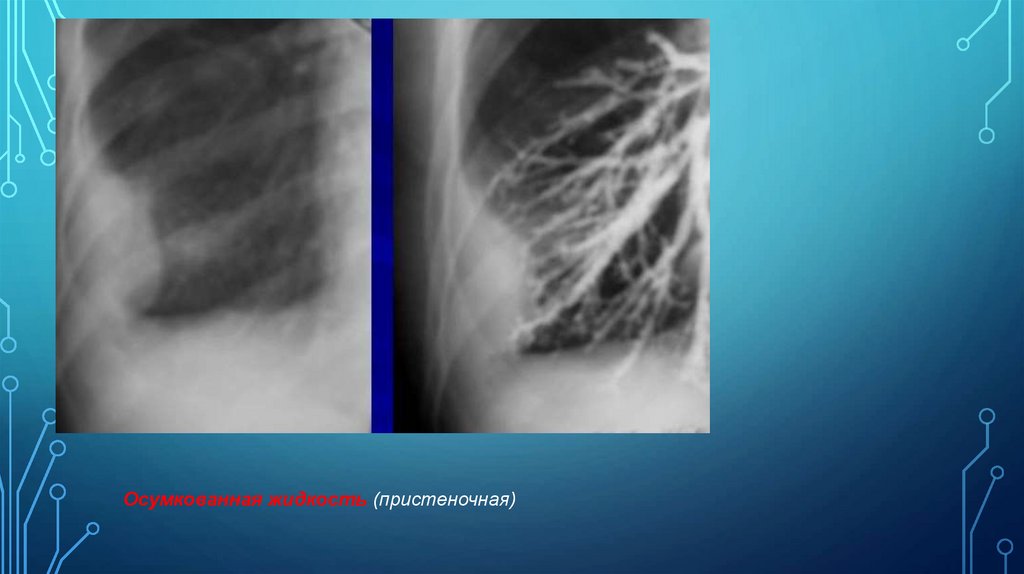

Б)

Осумкованная жидкость (пристеночная)

в краеобразующих проекциях имеют полуовальную форму, латерально широким основанием

примыкает к внутренней поверхности грудной стенки, медиально выпуклым контуром

обращена в сторону легкого. Границы затенения с грудной стенкой плавные, с образованием

тупых углов